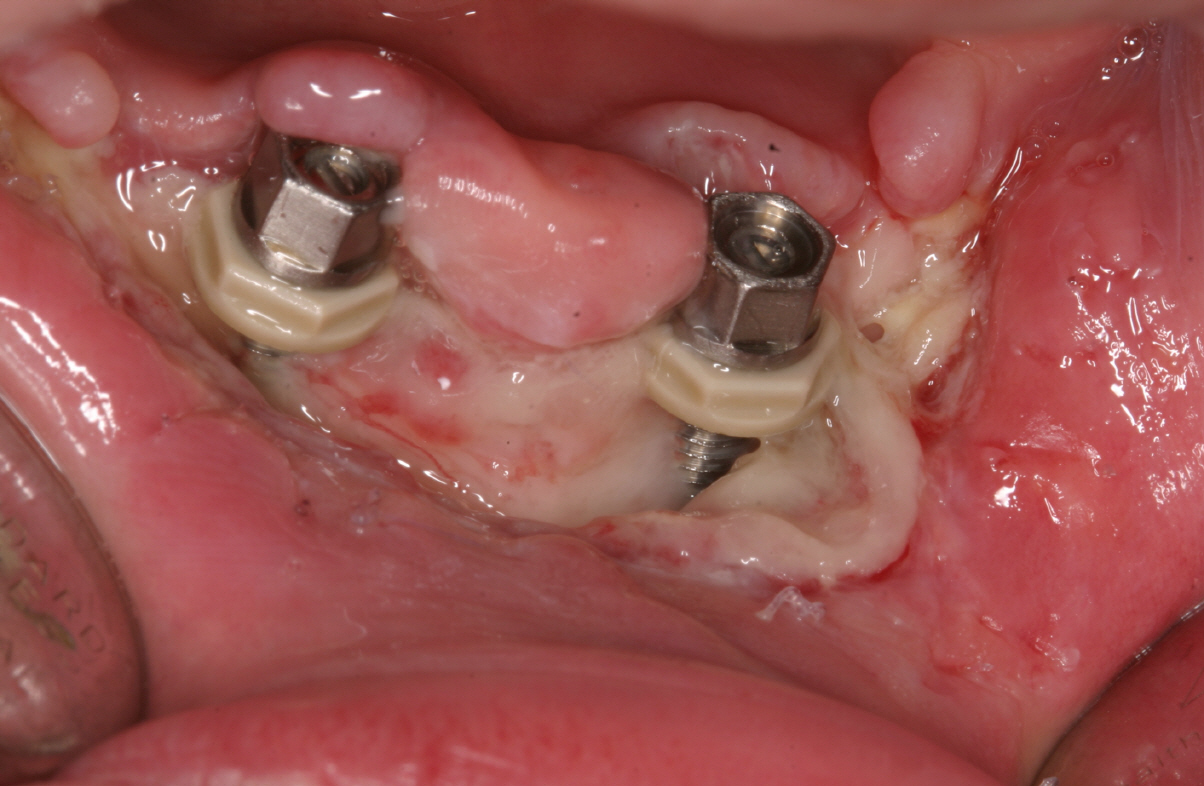

In seltenen Fällen kann sich bei der offenen Einheilung (d.h. das Implantat heilt also nicht unter der geschlossen Schleimhaut ein, sondern ragt mit der Schulter in die Mundhöhle) die Abdeckschraube (Verschlussschraube) lösen. Dies führt nicht selten zu einer verständlichen Beunruhigung des Patienten, weil er glaubt, dass ganze Implantat sei locker. Ein wieder Festschrauben der Kappe durch den Implantologen löst in Sekundenschnelle das Problem.